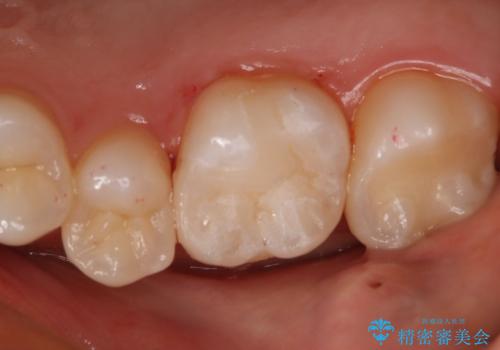

- 咬んだ時に右下奥歯に痛みがあるとの事で来院された患者様です。

歯の神経は壊死していたため、精密根管治療と補綴治療を計画しました。

セラミックでの治療を希望されたので補綴はオールセラミッククラウンでの治療を選択しました。

痛みは完全に取り除かれ、咬合時の違和感もなく経過は良好です。